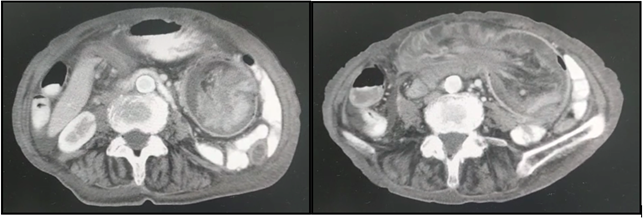

Tomografía abdominopélvica con contraste oral y endovenoso: Se observa derrame pleural bilateral. Por otra parte, a nivel centroabdominal y con extensión hacia flanco izquierdo se identifica extensa imagen redondeada con estructuras vasculares en su interior y contenido aéreo compatible con intususcepcion intestinal (invaginacion colocolónica) con una extensión aproximada de 10cm con refuerzo parietal ante la administración de contraste endovenoso. Presencia de moderado líquido libre multicompartimental, sin evidencia de niveles hidroaéreos.

IMAGEN 1. Tomografía axial que evidencia invaginación colocolónica.